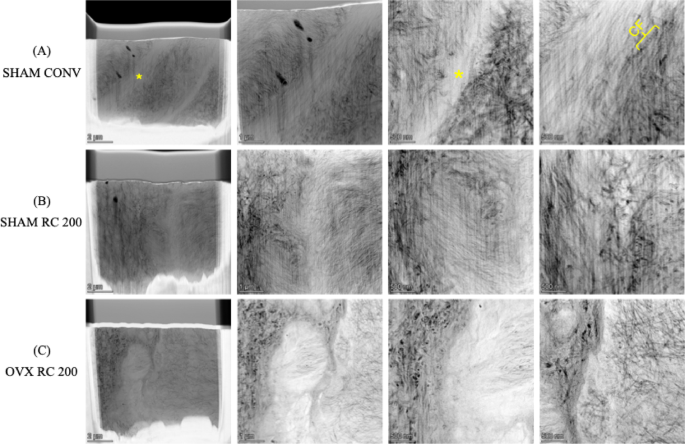

High-Angle Annular Dark-Field Scanning Transmission Electron Microscopy (HAADF-STEM) images allow for the investigation of bone collagen arrangement and hydroxyapatite crystal distribution at the nanometer scale, enabling a comparison of bone formation near the conventional implant surface versus the surface functionalized with RC. Due to the cracks at the implant-bone interface, samples spanning the interface between pre-existing (old) and de novo (new) bone were prepared by Focused Ion Beam Microscopy (FIB). Resulting HAADF-STEM images are in (Fig. 10). Collagen fibers are visible in TEM as alternating dark and light zones along the length of the fiber, but their visibility depends on the orientation of the collagen fibers in the Section30. When collagen fibers are in the plane of the sample, the alternating dark and light zones are visible (marked CF in top row). However, when the fibers are out of plane, circular dark spots appear, which are indicative of their orientation cut in cross-Section30.

In Fig. 10, STEM imaging reveals the collagen fibril patterns30,31. In all samples, a bright, highly mineralized interface is visible between old and new bone, with collagen fibers aligned in the plane of the image and out. The newly formed bone (on the left side of the images) displays rapid deposition and a disorganized, woven bone structure.

In the SHAM CONV group, a highly mineralized cement-line-like interface is observed. At higher magnification, the interface shows aligned collagen fibrils at the boundary, with less organized bone on either side. In the newly formed bone, dark circular holes, likely artifacts from focused ion beam (FIB) milling, are visible, possibly representing osteocyte canaliculi preferentially milled by the ion beam. The older bone shows collagen fibers that are perpendicular to the plane of the image, resulting in dark circular regions30 (Fig. 10A).

In the SHAM RC 200 group, the newly formed bone pattern shows less organized collagen fibrils compared to the older bone, which exhibits a well-organized collagen fibril pattern with clear banding visible in the plane of the image. This uneven pattern suggests that the new bone is still immature, having been rapidly deposited, and can be classified as woven bone. The interface between the new and old bone appears bright, likely indicating a highly mineralized cement line or suggesting pauses and restarts in the bone formation 32 (Fig. 10B).

In the OVX RC 200 group, the new woven bone pattern is evident, showing less organized collagen fibrils. The lamellar bone in the OVX RC 200 group is less organized compared to that in the SHAM RC 200 group (Fig. 10C).

HAADF-STEM images of the interface between new woven bone and pre-existing old bone for SHAM CONV, SHAM RC 200, and OVX RC 200. From left to right: Low magnification to higher magnification. Note that the new bone is located on the left side while the old bone is located at the right side of the images. Note the cement-line-like interface marked by an asterisk. CF = Collagen fibril.